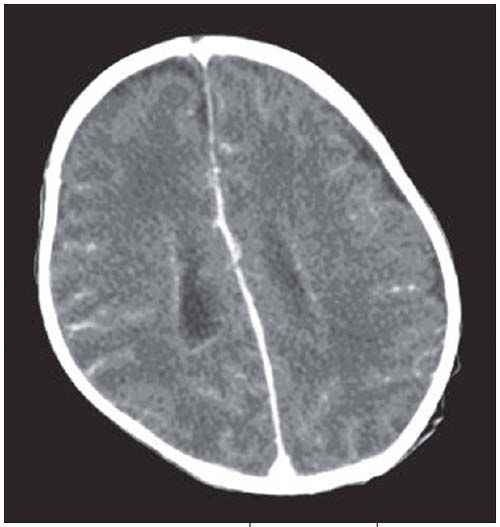

Figure 3 – Contrastenhanced CT scan shows enhancement of the ependyma of the lateral ventricles, consistent with ventriculitis. Slight prominence of the cisterns at the left cerebral convexity and right frontal region is also present.

On day 2 of hospitalization, a cranial ultrasonogram revealed hydrocephalus, with echogenic ependyma of the lateral ventricles, related to ventriculitis (Figure 1). Linear synechiae noted within the ventricles were characteristic of inflammation. The 3rd and 4th ventricles were normal. The findings represented a noncommunicating hydrocephalus at the level of the Monro foramen. A week later, a follow-up ultrasonogram showed resolution of the hydrocephalus and reabsorption of the intraventricular echogenic strands (Figure 2); there was no evidence of a focal brain lesion. A contrast-enhanced CT scan on day 17 revealed enhancement of the ependymal lining of the lateral ventricles with no hydrocephalus (Figure 3). Slight cisternal enlargement at the left lateral cerebral convexity and right frontal region, consistent with sympathetic effusion (exudative effusion caused by disease in nearby structure), was also present. The parenchyma was normal.